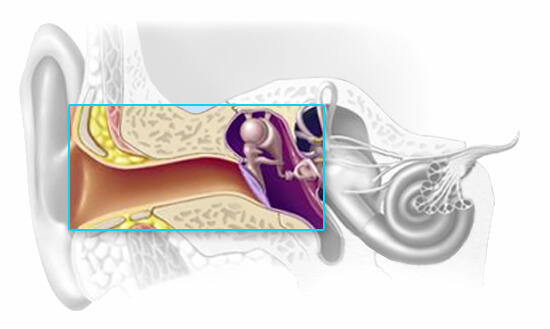

Conductive hearing loss

A conductive hearing loss is caused by any condition or disease that impedes the conveyance of sound in its mechanical form through the middle ear cavity to the inner ear. A conductive hearing loss can be the result of a blockage in the external ear canal or can be caused by any disorder that unfavorably effects the middle ear’s ability to transmit the mechanical energy to the stapes footplate.

This result is the reduction of one of the physical attributes of sound called intensity (loudness), so the energy reaching the inner ear is lower or less intense than that in the original stimulus.Therefore, more energy is needed for individuals with a conductive hearing loss to hear sound, but once it’s loud enough and the mechanical impediment is overcome, the ear works in a normal way. Generally, the cause of conductive hearing loss can be identified and treated resulting in a complete or partial improvement in hearing. Following the completion of medical treatment for causes of the conductive hearing loss, hearing aids are effective in correcting the remaining hearing loss.